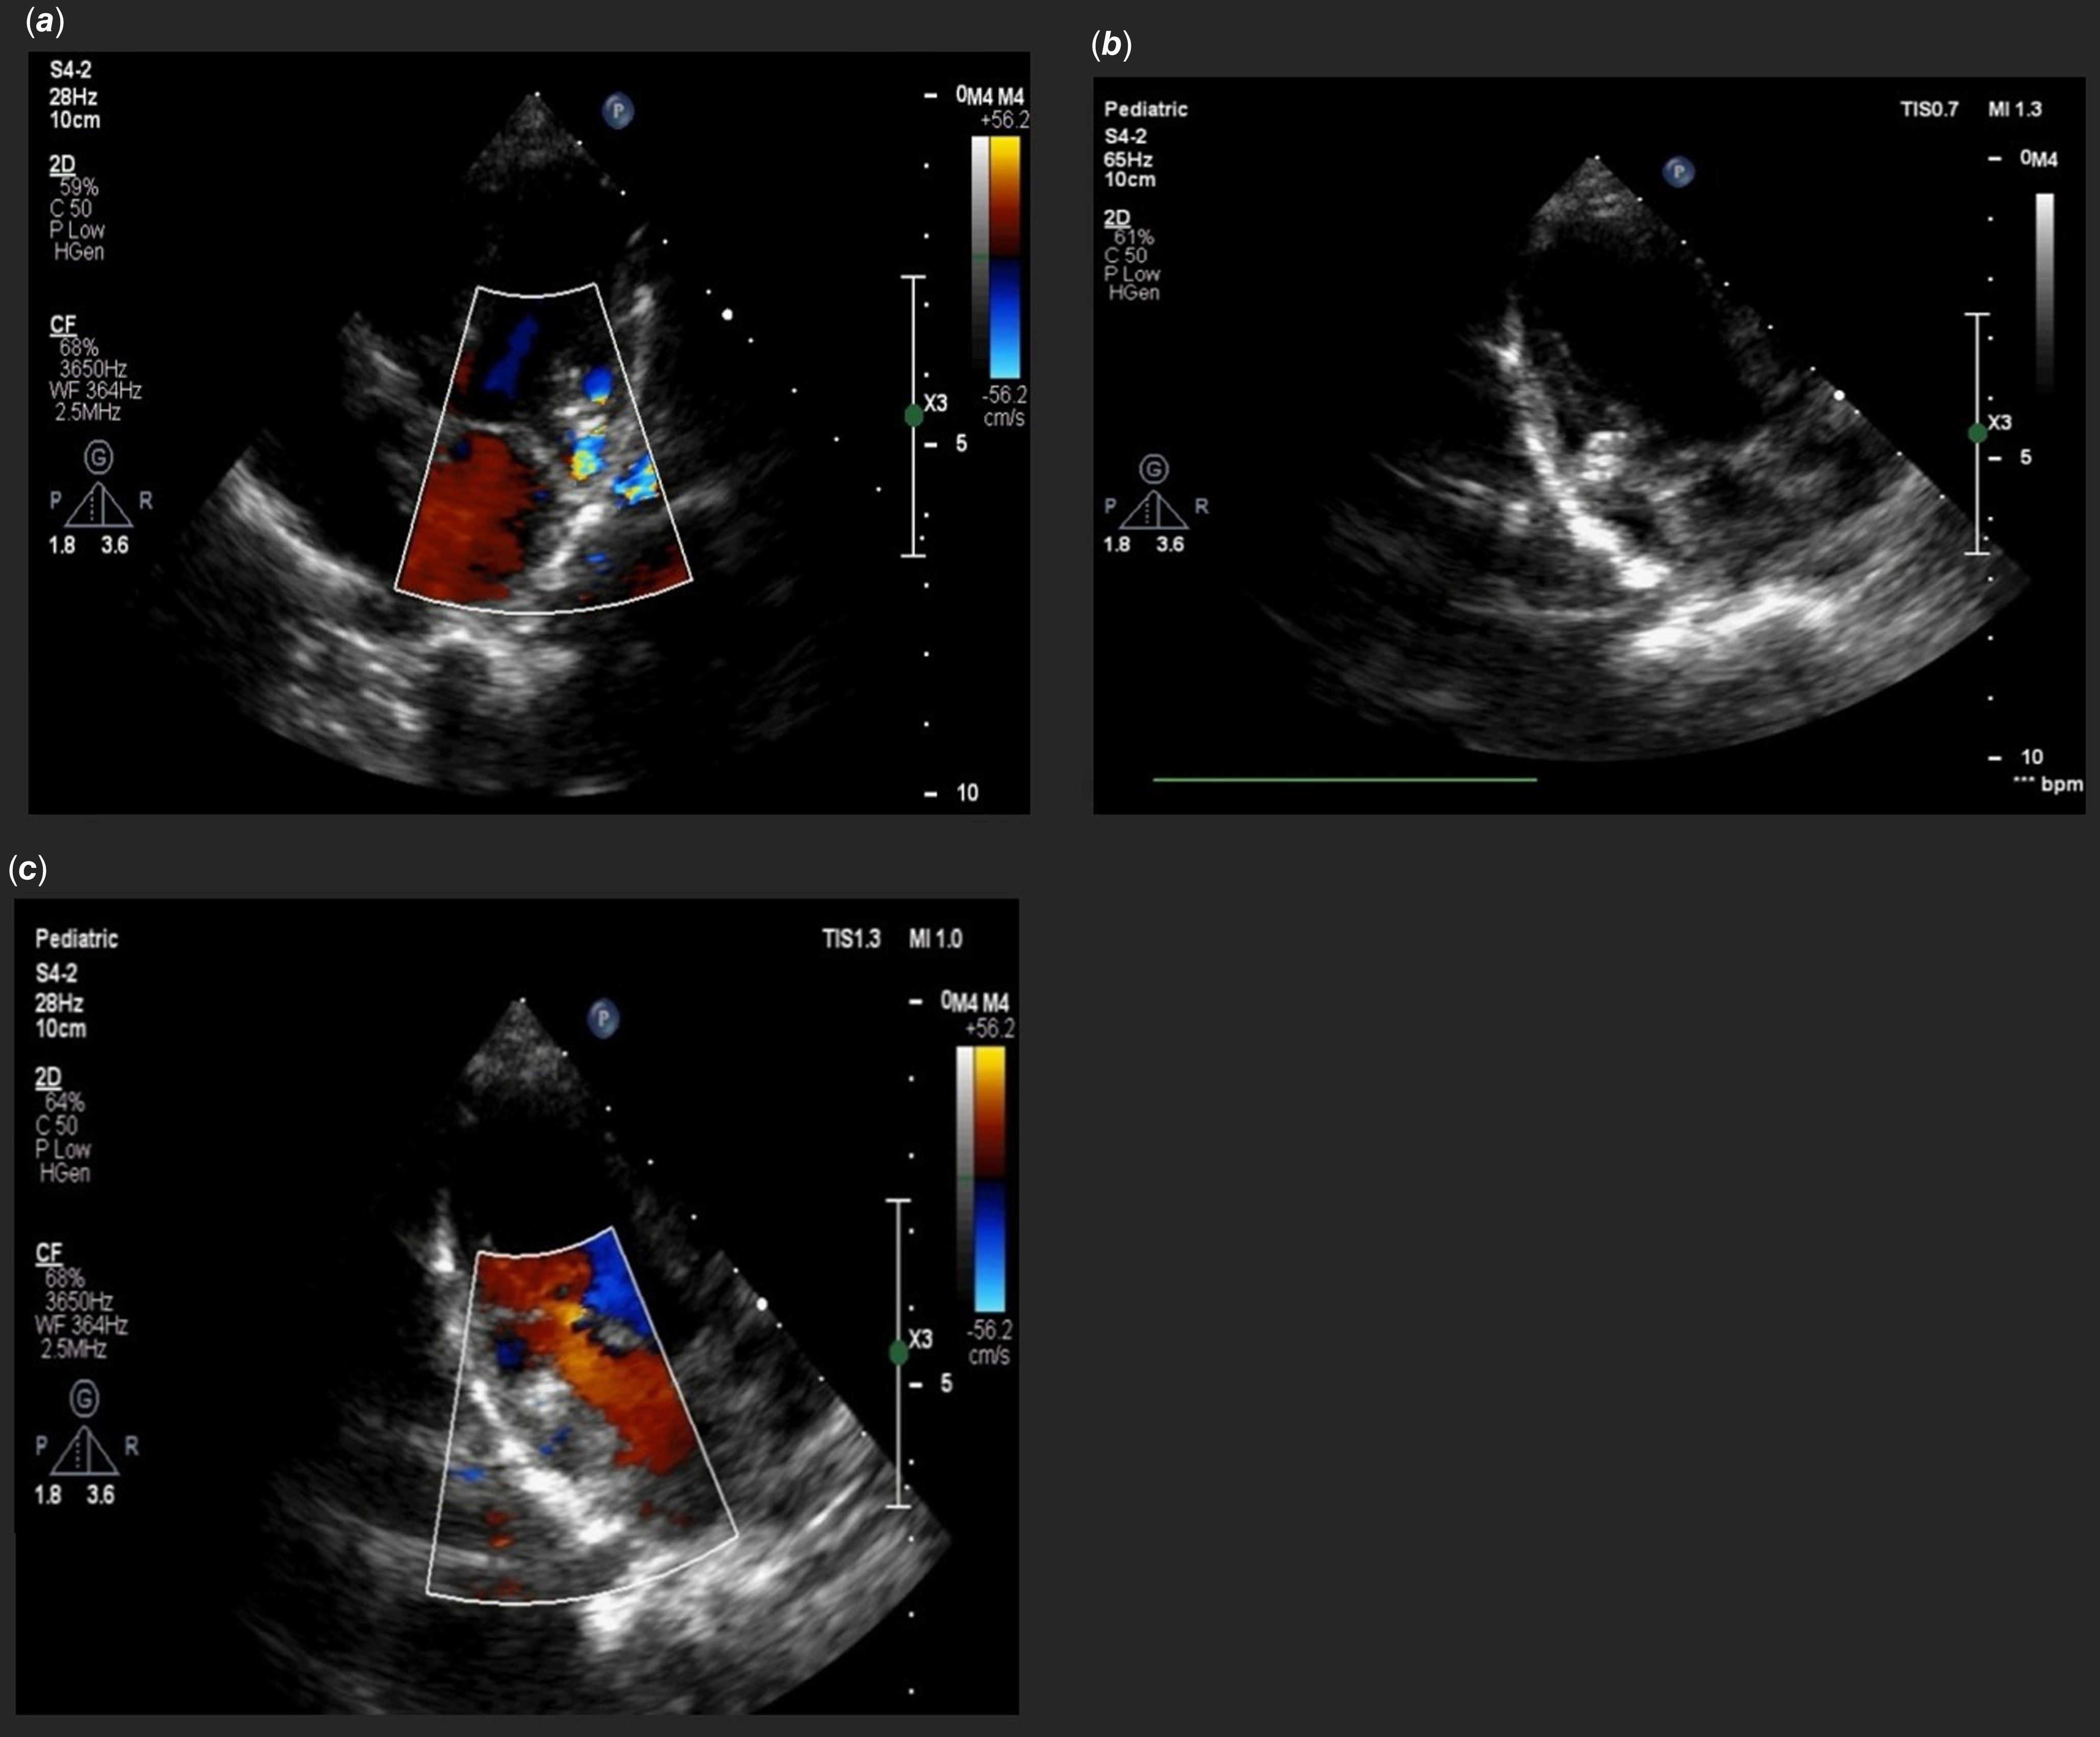

We report the case of an 18-month-old male, born full-term at 40 weeks without neonatal complications. At admission, his weight was 12 kg. The patient was acyanotic and asymptomatic. Cardiac examination revealed a prominent 3/6 systolic ejection murmur; however, there were no signs of heart failure or organomegaly, and weight gain was normal. Chest radiography indicated slight cardiomegaly, while the electrocardiogram showed sinus rhythm with a normal axis and no ST or T wave changes. A 2D and Doppler echocardiogram identified a dilated coronary sinus due to a left ventricular to coronary sinus fistula, with a jet waist measuring 3 mm and velocity around 4 m/sec. The pressure gradient across the fistula was noted at 60 mm Hg (Figure 1). Additionally, moderate right atrial enlargement and right ventricular enlargement were observed, with an Left Ventricular Ejection Fraction of 60%. Pre-procedural CT angiography provided a detailed anatomical evaluation, showing a width of 3 mm and a length of 4 mm (Figure 2). Catheterization revealed normal right atrial pressure and pulmonary artery pressures of 30/15 mmHg (mean 22 mmHg). Oxygen saturation levels indicated a significant left-to-right shunt with Qp/Qs of 1:1.5. Two catheterisation strategies, antegrade and retrograde, were evaluated for the occlusion procedure. Due to the intricate anatomical structure and the demanding wire-snaring location, the antegrade approach was favoured. This strategy facilitated traversal through the defect from the left ventricle to the coronary sinus, with successful snaring executed in the right atrium. In contrast, utilizing the retrograde approach would have necessitated wire snaring within the left ventricle, which was anticipated to be more challenging than the antegrade method. To close this fistula, a 4 French pig-tail catheter, which had been appropriately sized by trimming its tip, was first inserted into the left ventricle via the femoral artery. Subsequently, a 0.018-inch guidewire was used to traverse the fistula, and the wire was snared in the right atrium. After successfully navigating the fistula pathway, it was occluded using a Piccolo device (5 mm × 4 mm). The selection of this device was due to its optimal flexibility and the ability to conform to the anatomical configuration of the lesion. To ensure precise placement and maximum stability, the first disc of the device was positioned in the left ventricle, the body of the device within the fistula, and the final disc in the coronary sinus. Given the enlarged and dilated nature of the coronary sinus, positioning the edge of the device at the base of the coronary sinus did not interfere with the sinus pathway (Figure 3). Serial echocardiographic follow-ups before discharge and at 1, 6, 12, 24, and 32 months post-procedure showed minimal residual shunt initially, which resolved completely in subsequent studies with no shunt present at the fistula site (Figure 4). A 24-hour Holter monitor post-discharge confirmed normal sinus rhythm without ectopic beats or arrhythmias.

Figure 4. (a, b) Apical four-chamber view showed device in 2D and colour Doppler that revel no residual shunt from left ventricular to coronary sinus was remain (c) parasternal long-axis view with colour Doppler with no significant residual shunt. 2D, two-dimensional; CF, colour flow Doppler.